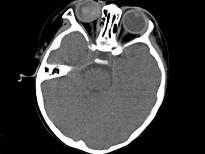

问题 男,2岁、右眼白瞳症1个月,CT影像如图,最可能的诊断为()

选项 A.眼球内寄生虫病 B.永存原始玻璃体增生症 C.脉络膜骨病 D.Coats病 E.视网膜母细胞瘤

答案 E